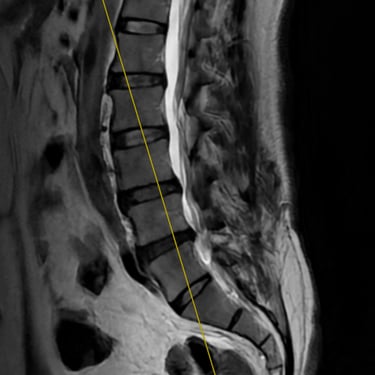

Inestabilidad de la Columna Lumbar: Tratamiento con Fijación Transpedicular y TLIF

La inestabilidad de la columna lumbar ocurre cuando los segmentos vertebrales pierden su alineación y soporte normal, generando dolor lumbar crónico, limitación funcional y, en algunos casos, compresión de las raíces nerviosas. Cuando el tratamiento conservador no resulta efectivo, la fijación transpedicular (FTP) asociada a la fusión intersomática transforaminal (TLIF) representa una alternativa quirúrgica eficaz. Este procedimiento permite estabilizar el segmento afectado, descomprimir las estructuras nerviosas y restaurar la biomecánica de la columna. La combinación de fijación y fusión reduce el dolor, mejora la estabilidad vertebral y favorece una recuperación funcional segura y progresiva.